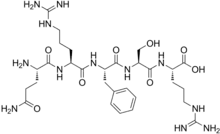

| Opioid peptides | Skeletal molecular images |

| Adrenorphin |  |

| Amidorphin |  |

| Casomorphin | |

| DADLE | |

| DAMGO |  |

| Dermorphin | |

| Endomorphin |  |

| Morphiceptin |  |

| Nociceptin |  |

| Octreotide |  |

| Opiorphin |  |

| TRIMU 5 |  |